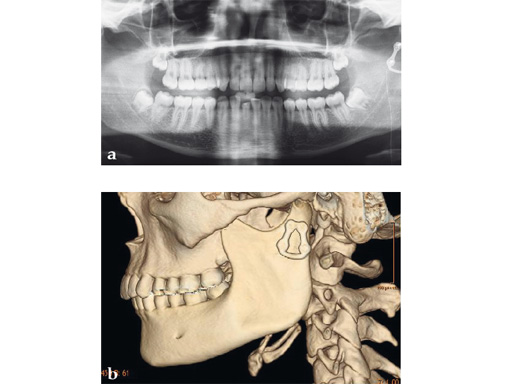

Case 2

Case provided by Michael Rasse, Innsbruck, Austria